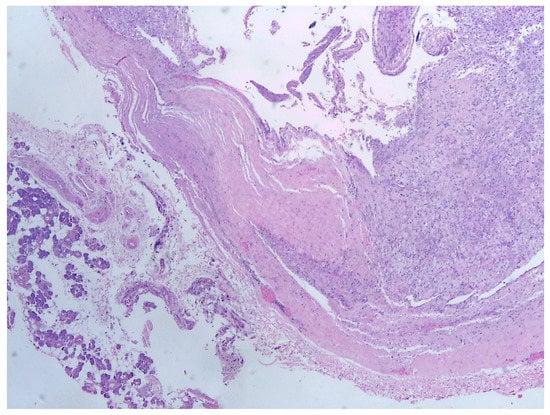

5. Histology